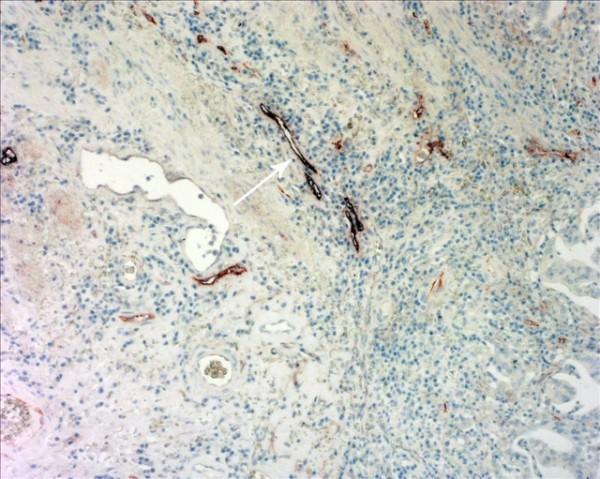

Intratumoral LVD (I-LVD) and peritumoral LVD (P-LVD) of 123 patients with primary gastric cancer were assessed after staining with D2-40, and confirmed by double staining with D2-40/CD34. Proliferative activity of lymphatics endothelium was evaluated by double staining with D2-40/Ki-67. The associations were analyzed between I-LVD/P-LVD and the expression level of VEGF-A, VEGF-C, VEGF-D and the receptor VEGFR-3, which was measured by immunohistochemistry (IHC). The correlations of I-LVD and P-LVD with patient prognosis were also valued.

(1) The peritumoral lymphatics (PTLs) were relatively enlarged with dilated lumen compared with the intratumoral lymphatics (ITLs). Increased P-LVD was significantly higher than I-LVD (P < 0.05). (2) P-LVD was found significantly associated with lymph node metastasis (LNM) (P < 0.001), lymphatic vessel invasion (LVI) (P < 0.001), VEGF-C (P = 0.003), VEGF-D expression level (P = 0.005) and VEGFR-3 expression level (P < 0.001) in peritumoral tissues, despite no significant association was found between above variants with I-LVD. However, increased I-LVD was demonstrated to be associated with decreased tumor volume (P < 0.001). Neither I-LVD nor P-LVD was correlated with VEGF-A expression (P > 0.05). (3) Proliferative activity of lymphatics endothelium was observed in PTLs, in spite of ITLs. (4) Increased P-LVD, but not I-LVD, was indicated to be an independent risk factor for lymph node metastasis by multivariate logistic regression analysis, and was related to worse disease-free survival and overall survival.